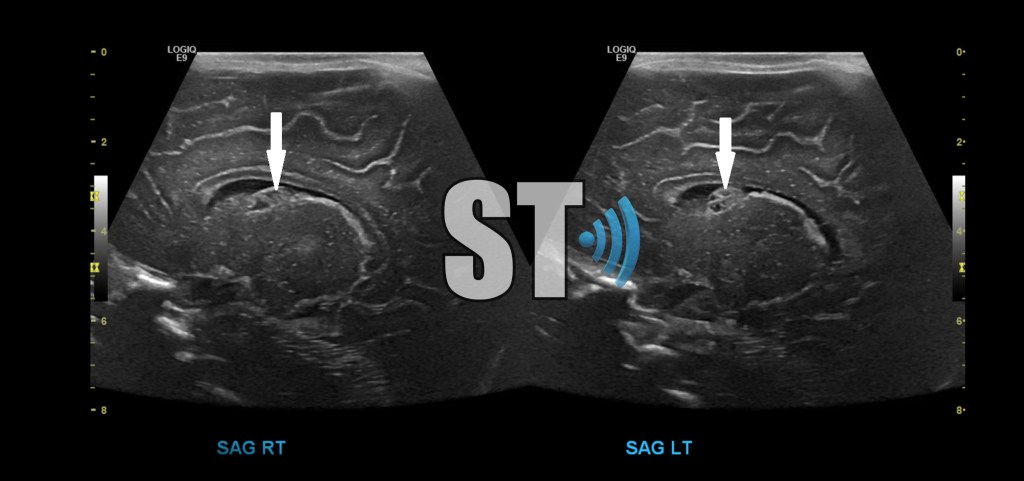

Bilateral grade I IVH, close follow up is recommended to ensure complete resolution.

Coronal and Sagittal images of a premature neonate with bilateral grade III IVH, notice the lack of gyri and sulci indicative of a extreme prematurity.